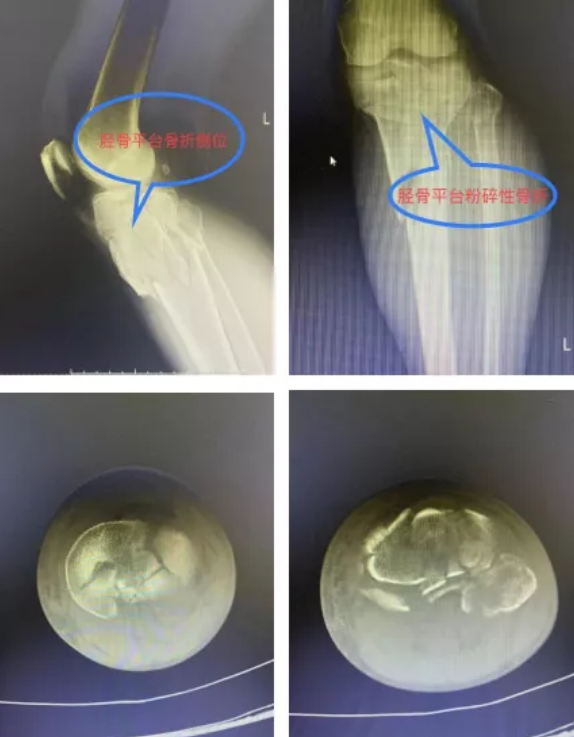

到达医院后,关节创伤骨科值班医生袁文泽和主治医师刘超迅速接诊,在查看伤情后随即安排检查,X光结果提示:左膝胫骨平台内外后三个方向塌陷骨折,需要手术治疗。经过一个星期的跟骨牵引、消肿、止痛抗凝等治疗,吴师傅伤情稳定,10月18日,关节创伤骨科主任王显勋根据伤者具体情况,选择为其进行内外后三个方向钢板固定术,通过胫骨平台内外侧两块钢板巧妙恢复胫骨平台关节面的平整,同时将骨折固定牢靠,两个小时后吴师傅被顺利推出手术室。